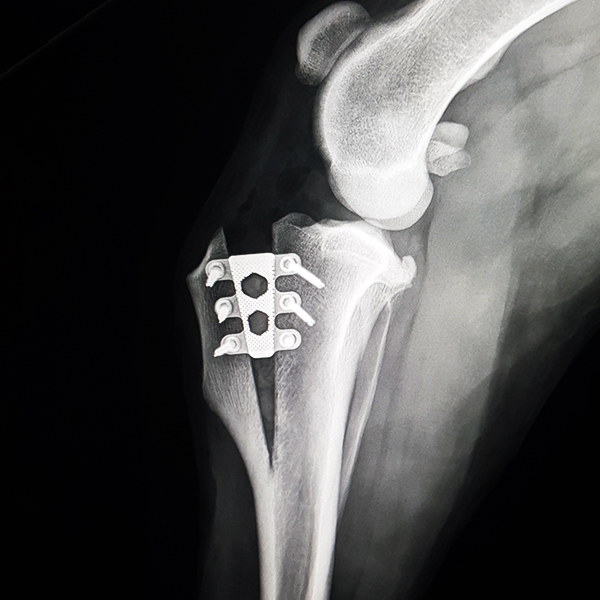

CrCL Ruptures in Small Breeds:

Osteotomies or extra capsular repair

CrCL Ruptures in Small Breeds: Should we use osteotomies instead of extra capsular repair?

TTA RAPID®

Learn how to perform CCL Repair with TTA RAPID®

Tiny TTA RAPID®

Learn how to fix CCL Ruptures in Tiny Animals with the Tiny TTA RAPID® System